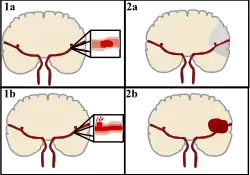

Cévní mozková příhoda (CMP, též ictus, iktus, mozková mrtvice nebo mozkový infarkt) je náhle se rozvíjející postižení určitého okrsku mozkové tkáně vzniklé poruchou jejího prokrvení. K této poruše může dojít buď na podkladě uzávěru mozkové tepny (tzv. ischemická CMP, obrázek 1a,2a), nebo na podkladě krvácení z mozkové cévy (tzv. hemoragická CMP, obrázek 1b,2b). Cévní mozková příhoda je akutní stav, vyžaduje neodkladnou lékařskou pomoc. Včasné rozpoznání a okamžitý transport do specializovaného centra je nutný pro záchranu pohyblivosti a řeči pacienta. Během jedné minuty odumírají miliony buněk. Doprava, diagnostika a léčba proto na sebe musí navazovat v minutách. Pokud se jedná o krevní sraženinu a její rozpouštění – trombolýza – začne do 60 minut po vzniku příznaků, pacient má 70% naději na úplné uzdravení.